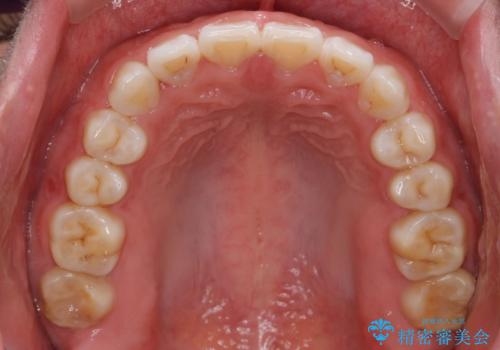

インビザライン 気になるすきっ歯の改善

- 上下顎前歯部の空隙が気になるので治したいと当院にいらっしゃった方の症例です。

非抜歯、インビザラインによる矯正治療により歯と歯の隙間および前歯の上下の隙間を閉じ切りました。